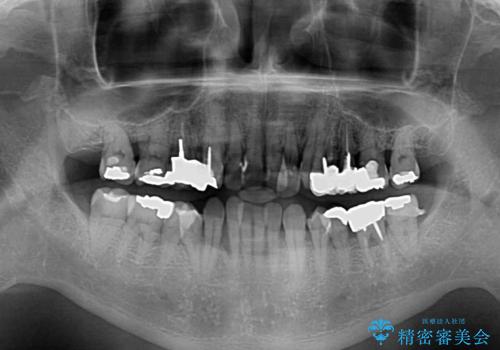

全体的に中等度の歯周病と診断されたため、歯周外科処置やインプラントによる咬合回復から進めて行き、矯正治療による歯列改善を行った後にオールセラミッククラウンにて補綴することとしました。

歯槽骨の再生治療を行ったため、外科処置後の静置期間がながくなり、4年弱の治療期間となりました。

初診来院時には矯正治療を行うことは想像していなかったようで、治療後には咬みやすさだけでなく、前歯が大変審美的に仕上がり、患者様には大変満足していただきました。